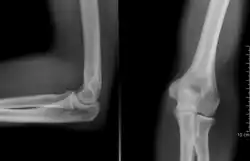

Uma radiografia simples do cotovelo